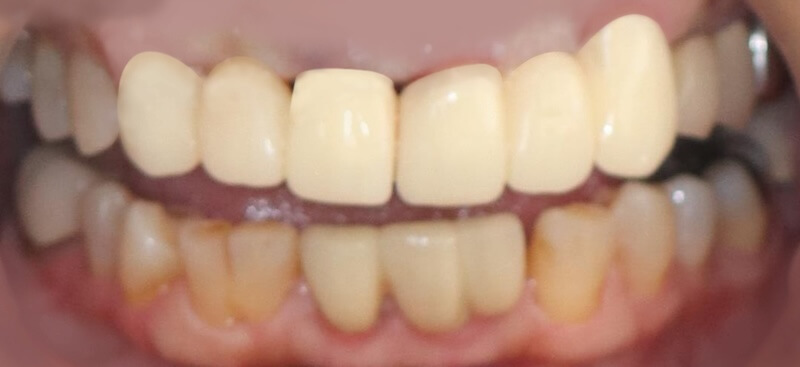

在這個相對健康的牙周環境狀態下,我們利用DSD數位微笑設計,全數位化的口內掃描並製作出第二組臨時假牙,透過這組假牙置放在口內和她討論未來正式假牙的外型與顏色。

經過第二組臨時假牙的配戴,我的建議會是有兩處牙周相關的問題可以做改正:

- 原本兩顆正中門牙的長度並不一致,我們可以利用水雷射進行牙冠增長術。以不開刀的方式雕塑牙齦和內部的齒槽骨,也不需要縫合。讓兩顆正中門牙盡量達到視覺上長度一致。

手術完成後的兩三個月左右,製作正式的假牙。最終的假牙我們設計成兩組正中門牙和犬齒相連的牙橋,和原來六顆連在ㄧ起的設計相比,清潔會相對容易很多。Ms.H 對治療前後的明顯感受是:牙齦牙周的問題獲得滿意的解決以外,新的假牙的美觀度也有大幅的改善,花時間好好投資在自己身上,非常值得。未來規律定期回診好好的維護,相信能夠常保健康穩定的治療成果。